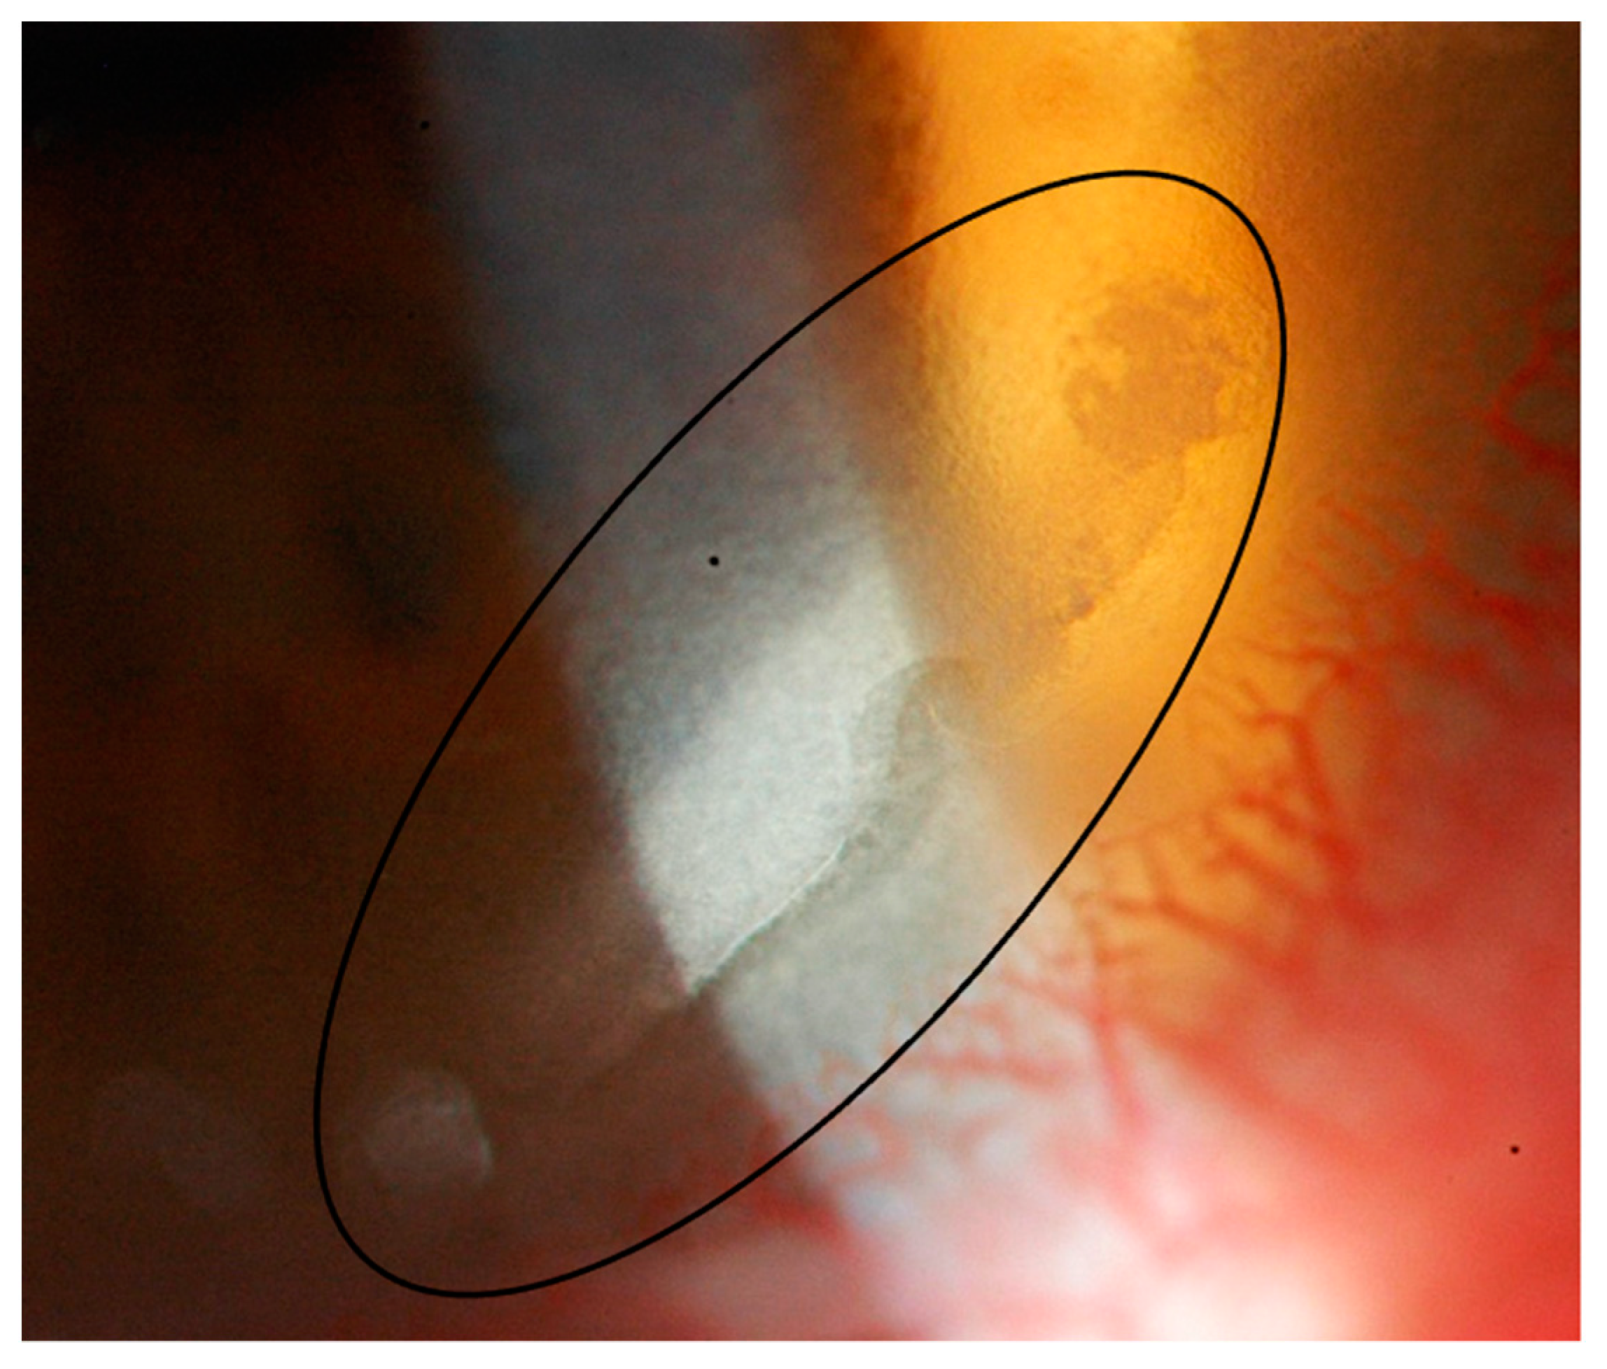

2.1. Case Report 1

2.2. Case Report 2